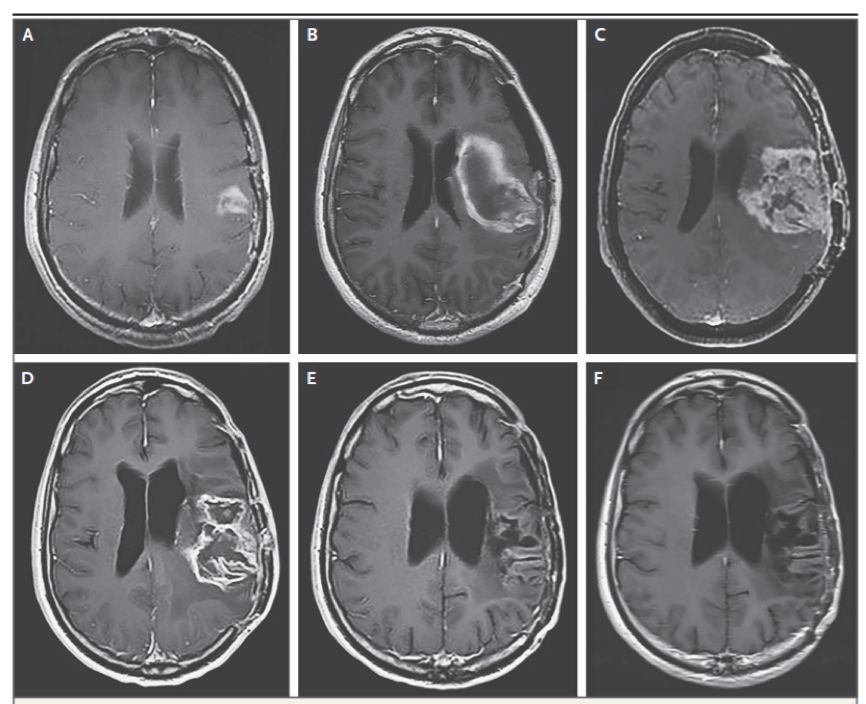

比如下面这位。

图A是治疗前的肿瘤,图C是溶瘤病毒治疗后,肿瘤进展。可以看出,这个时候肿瘤已经又长大了。医生只好换了一种叫洛莫司汀的化疗药物,试验宣告“失败”。

谁也没想到,仅一个疗程,肿瘤就开始出现好转(图D),到一年后,肿瘤已经完全消失了。即使停掉化疗一年后,肿瘤依然没有任何复发迹象(图F)。随访五年时,这个患者还活得好好的!